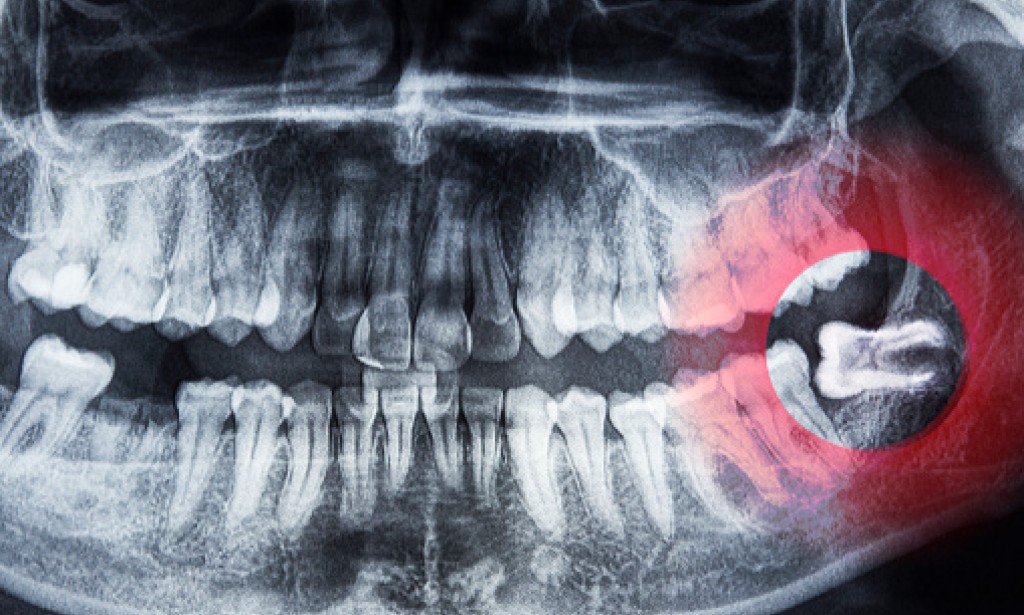

If you are feeling all these signs, thoroughly consult your dentist. He will help you by making a quick observation of your teeth. He might ask you for an X-ray report of your jawline to determine if the wisdom teeth are growing or not.

If it is growing, they might devise a special plan for you either you need to remove it or grow with braces.